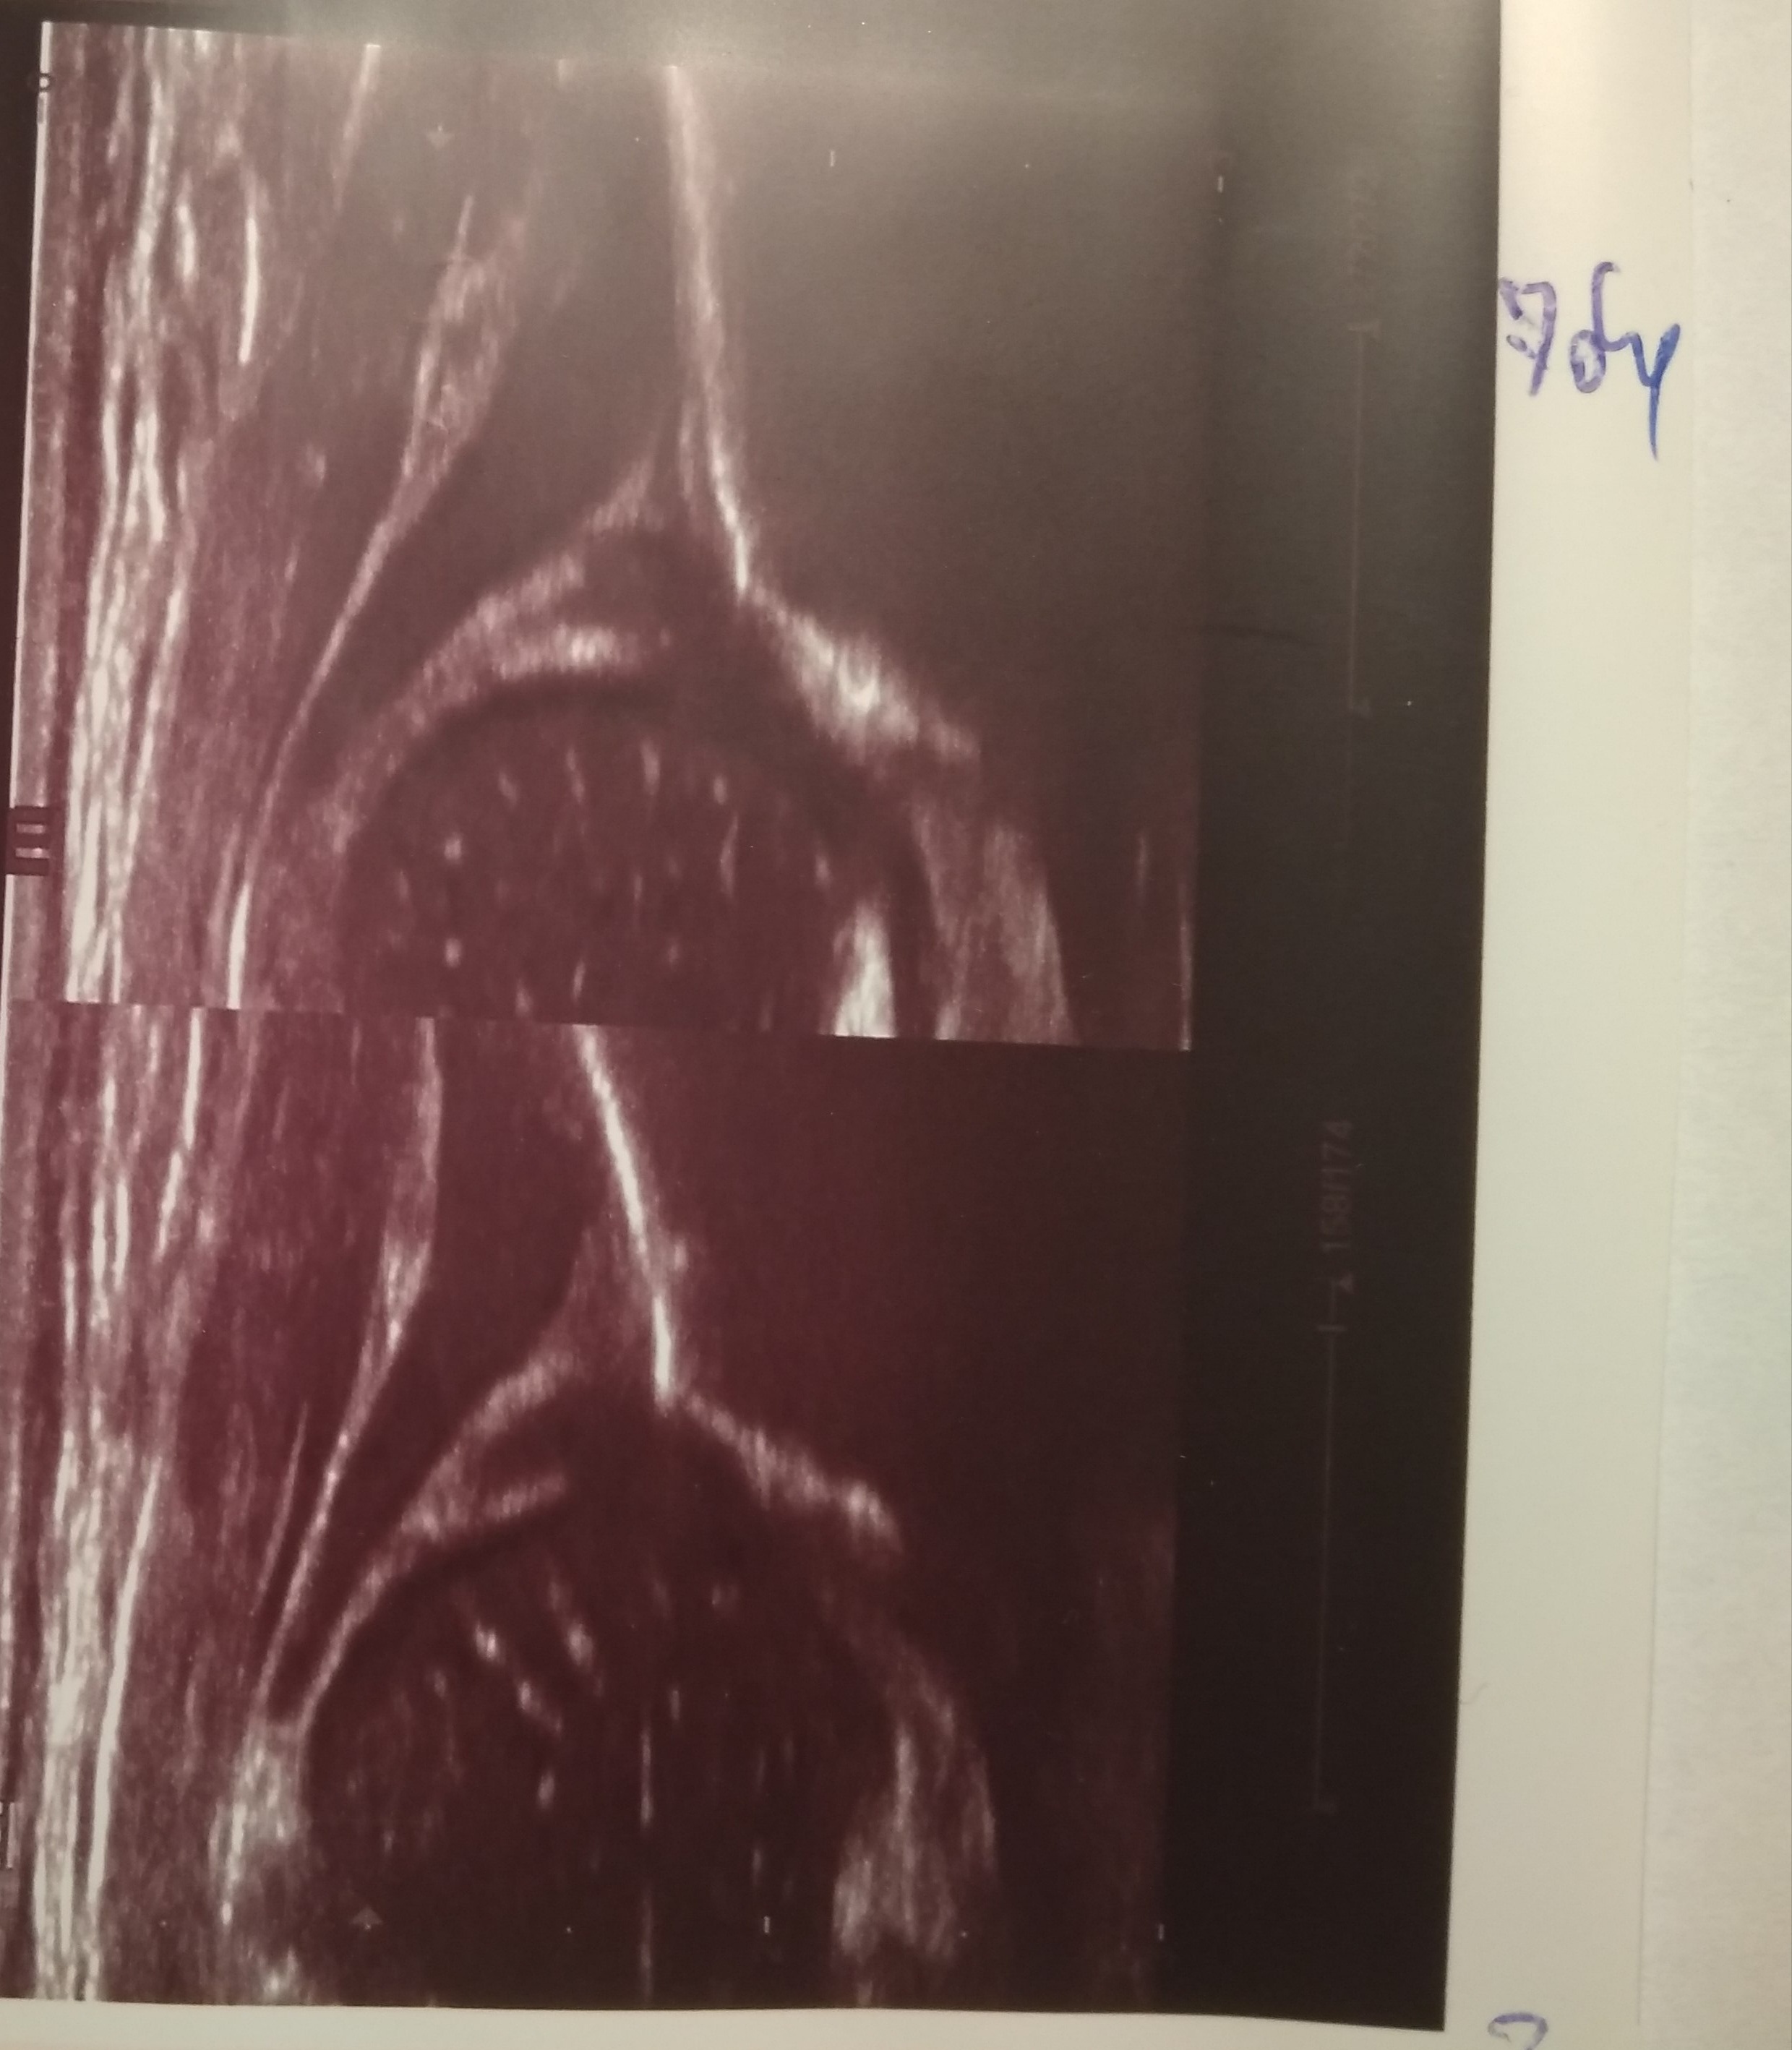

10 dzien dalej profilaktyka 17 godz

Typ P IIA L D ( gorny L)

21 dzien dalej profilatyka 17 gdozin dziennie( jedna kontrola 14 dzien brak dokumentacji w ! dzien śwąt)

TYP P IIa L IID kontrola za tydzien

28 dzien ż dalej profilaktyka 17 gdozin

Typ P GN L IIA kontrola za tydzien

35 dzien profilaktyka 17 godzin

Typ P IIa L IIa kontrola za 2 tyg

2 miesiace ż. dalej profilaktyka 17 godz stawy wlasciwie prawidłowe

Typ P I L GN kontrola za miesiąc